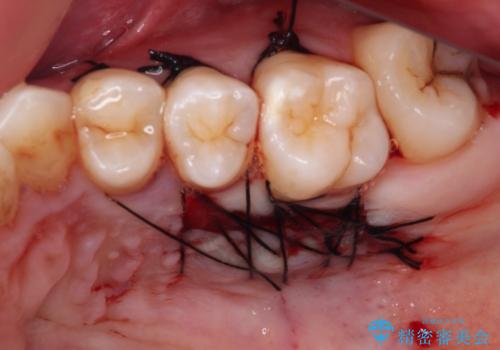

1回目の処置で多少は被覆され歯肉が厚くなりましたが、十分とは言えなかったため、2回目の処置を行いました。

2回目の処置後には十分な厚みと、十分な被覆量を獲得することができました。